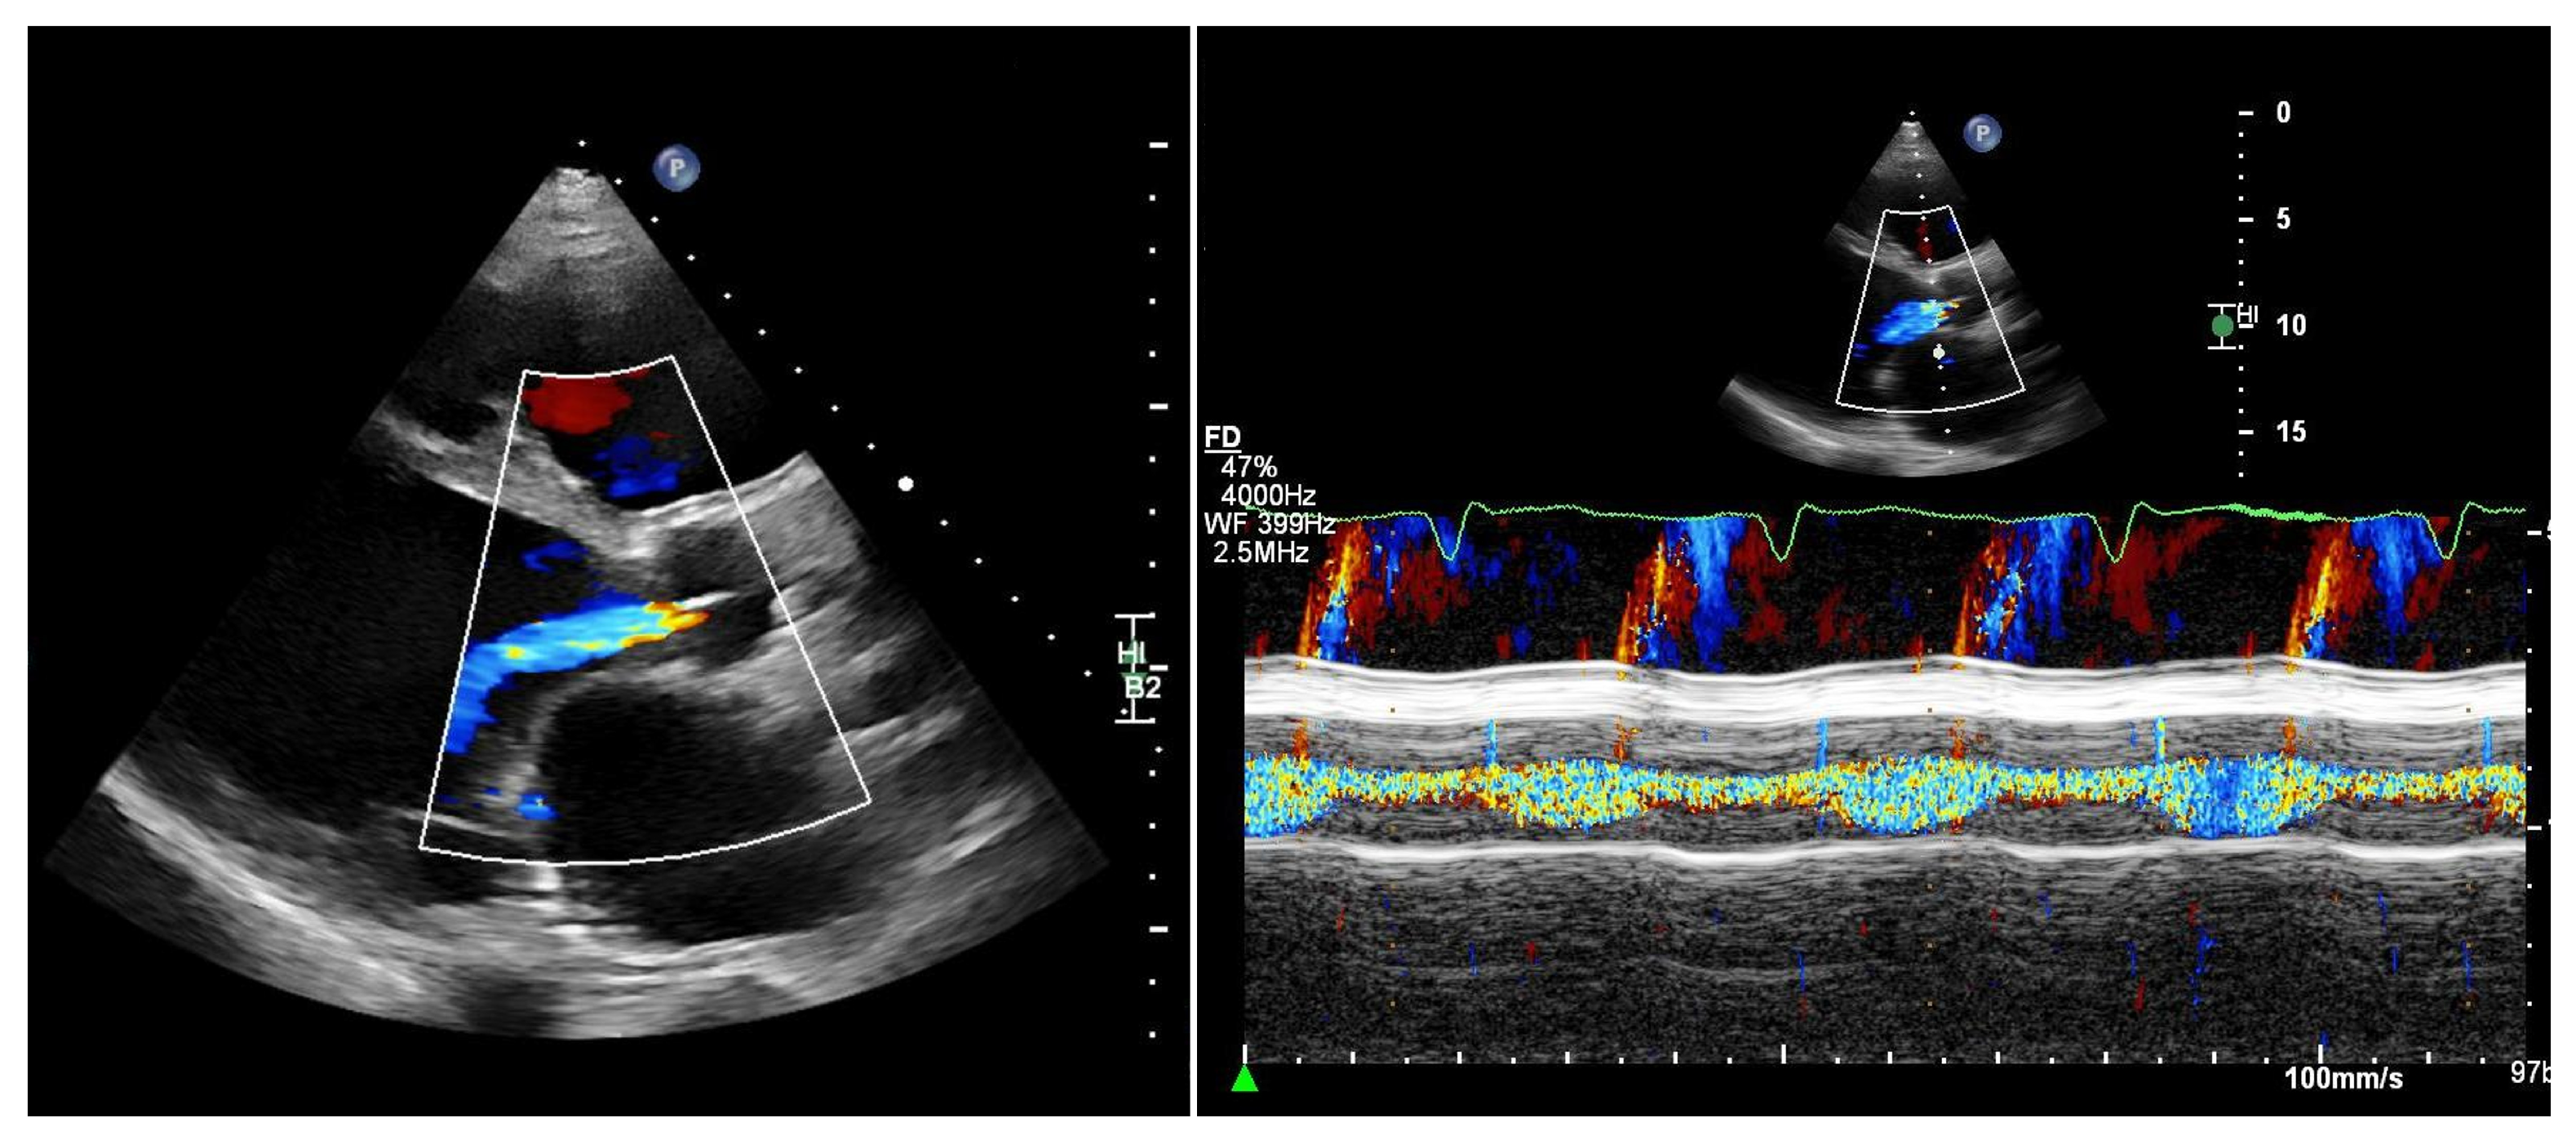

Quantifying aortic regurgitation (AR) in patients supported by a left ventricular assist device (LVAD) remains challenging. Conventional echocardiographic parameters are based on the assumption of isolated diastolic regurgitation, an assumption that often does not apply in the LVAD setting. In fact, holocyclic regurgitation (systolic and diastolic) is frequently observed, particularly in patients with more advanced AR (Figure 2).

Figure 2.

Patient with an LVAD and significant aortic regurgitation. Left: parasternal long-axis view. Right: M-mode of the aortic valve. M-mode color Doppler imaging clearly demonstrates both systolic and diastolic regurgitation.

Consequently, accurate quantification of AR should ideally be performed at specialized centers. Comprehensive assessment typically requires transthoracic echocardiography supplemented by transesophageal echocardiography to improve visualization of the regurgitant jet as well as right heart catheterization for detailed hemodynamic evaluation [24,25].

As a practical and readily available approach, vena contracta width and the ratio of the regurgitant jet width to the left ventricular outflow tract (LVOT) diameter may be used for semi-quantitative assessment:

- Vena contracta width ≥ 3 mm;

- Jet/LVOT ≥ 46% (compared with ≥60% in native aortic valves).

Both parameters suggest at least moderate AR [27]. Conversely, if the regurgitant jet is absent or only mildly detectable during diastole, mild AR may be assumed. In addition, progressive left ventricular dilatation over time supports the presence of chronic volume overload and is consistent with hemodynamically significant AR, particularly in symptomatic patients.

More recently, a novel transthoracic pulse-wave Doppler-based parameter obtained from a modified right-sided parasternal window has been proposed. By interrogating the LVAD outflow graft, diastolic flow acceleration and the systolic-to-diastolic peak velocity ratio (S/D ratio) can be calculated [28]:

- Outflow graft S/D ratio < 5.0 indicates at least moderate AR;

- Diastolic acceleration > 49 cm/s suggests significant AR.